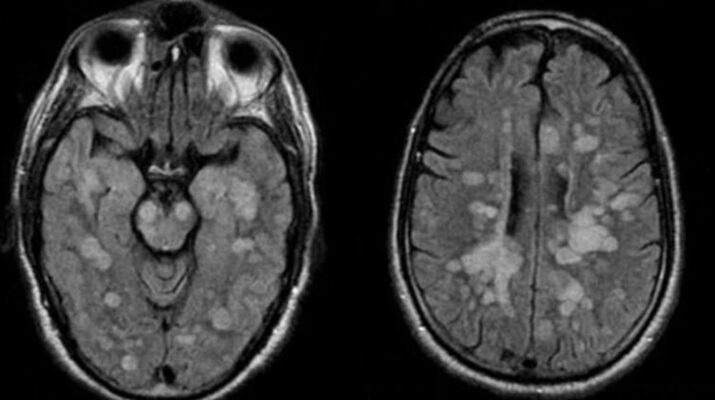

Talihsiz çocuğa vücudun bağışıklık sistemi kendisine saldırarak omurilik ve beynin şişmesine neden olan nadir bir akut yayılmış Ensefalit (ADEM) teşhisi koyuldu.

Braun’un Akut dissemine ensefalomyelit (ADEM) santral sinir sisteminin immun aracılıklı bir bozukluğuna yakalandığı bildirildi.